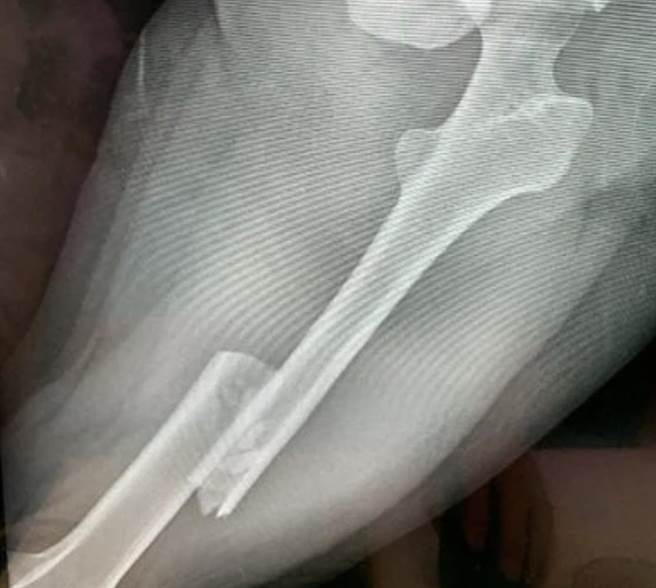

被害人的姐姐透過網路媒體發文,指稱妹妹覺得和男友交往沒有未來,因此在今年4月提議分手,但是,張姓男子卻認為兩人沒有分手的共識,因此在妹妹返營時開車兩度衝撞,造成全身多處骨折,包括顏面受傷、骨盆歪斜、左側股骨骨折,還有第5腰椎骨折恐怕造成癱瘓。